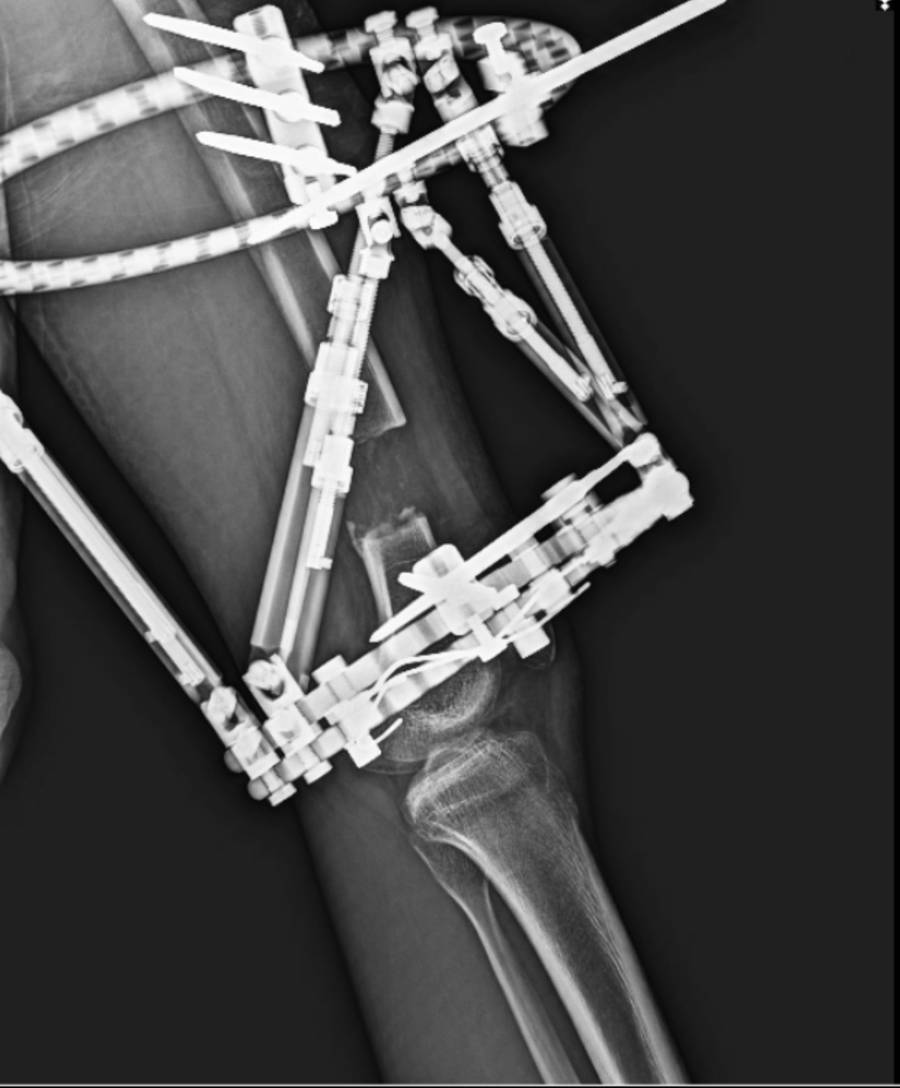

Kalkışım ve ekibi tarafından Tunay'a, bilgisayar destekli eksternal fiksatör denilen, dışardan tespit ile hem kemikte uzatma hem de dizilim osteotomisi (kemiğin kesilmesi) işlemleri aynı anda ve aşamalı şekilde uygulandı.

Hastanın uyluk kemiğinde osteotomi yaparak her gün 1 milimetre uzayacak şekilde tedavisini programlayan Kalkışım, uzatma ve düzeltme işlemi 40 günde bittikten sonra hasta konforu açısından dışardan koyulan tespit materyalini çıkarttı.

Kullanılan teknik ile yaklaşık 8 ayın sonunda Tunay'ın hem kemiği uzadı hem de deformitesi (vücudun bir bölümünün olması gerekenden farklı görünmesine veya çalışmasına neden olan bir organizmanın büyük bir anormalliği) düzelmiş oldu.

"Mevcut hastamız 18 yaşını doldurduğu için uzatma ameliyatını tercih ettik. Aralık ayının 15'inde ameliyatımızı gerçekleştirdik. Hastamızın tek sorunu kısalık değildi. Aynı zamanda bir deformite dediğimiz şekil bozukluğu da mevcuttu. Kullandığımız bilgisayar destekli, uzaysal 3 boyutlu düzeltme sağlayabilen sistemle tedavimizi planladık. Yaklaşık 1,5 aylık günlük rutinlerle deformite ve uzatma tedavimizi tamamladık. Sonrasında kestiğimiz kemiğin arasının kaynamasını bekledik. O kaynama da zaten gerçekleşmiş oldu."